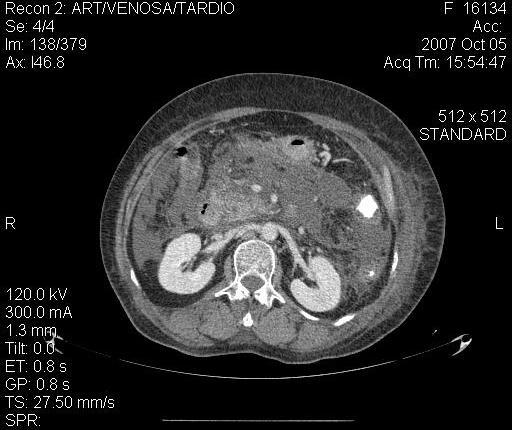

Isquemia mesentérica: Aguda y crónica